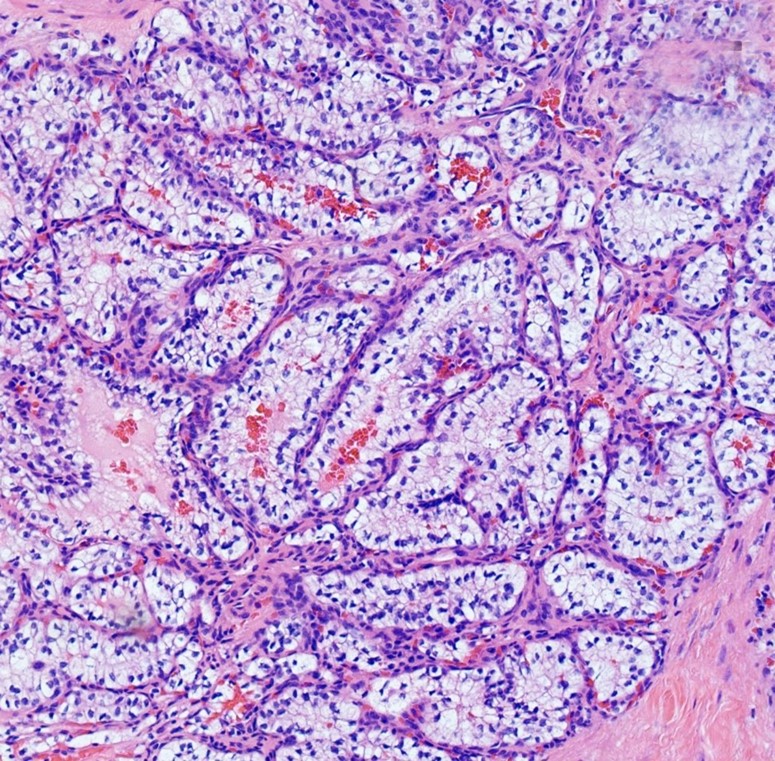

Microscopic examination revealed a clear cell neoplasm with tubular/glandular morphology (Figure 4). At this point, metastatic clear cell renal cell carcinoma (CCRCC) and clear cell papillary RCC were high in the differential diagnosis. However, the latter is extremely indolent with metastasis almost unheard of, and the patient's course of presentation with symptoms extending over a period of 4 years makes a malignant neoplasm less likely, favoring a benign entity.

On immunohistochemical staining the tumor cells were positive for pankeratin (AE1/AE3), PAX8, cytokeratin 7 (CK7), and epithelial membrane antigen (EMA). A CD10 stain showed equivocal weak focal staining. The stains for prostate specific antigen (PSA), prostate-specific acid phosphatase (PSAP), racemase (AMACR), CD30, and CD117 were negative (Figure 5).

Taking into consideration that the epididymal mass was present on a CT scan from 2019 (performed at another institution), and that no renal masses were present (which make metastatic renal cell carcinoma an unlikely diagnosis), the histologic features and immunohistochemical findings were considered to represent a papillary cystadenoma of the epididymis (PCE).